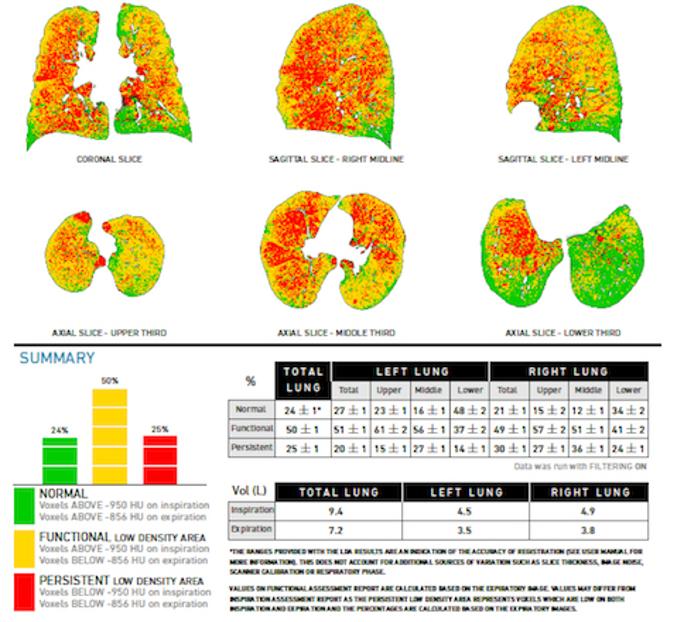

The PAIRR (Pulmonary Artificial Intelligence and Radiomics Research) Laboratory is a research unit of the Department of Radiology at UMass Memorial Medical Center and UMass Chan Medical School. Its mission is to develop, test, and implement innovative technology based on Artificial intelligence (AI) and Radiomics in the field of respiratory imaging.

The core research projects of the PAIRR Laboratory are based on accuracy and efficiency testing of novel AI and radiomics technologies. Additional research is focused on evaluating novel approaches to using these technologies, for example by combining or blending algorithms. Efficiency testing revolves around clinical algorithm implementation and the associated impact on work-flow and costs. Finally, a branch of research aims to develop and test mechanisms and metrics to quantify the “added-value” of novel technology to the clinical radiology workplace, and to analyze the increasing complexity of information generated by this technology.